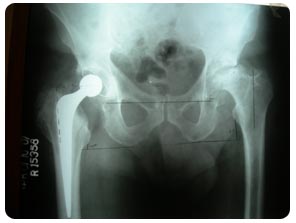

Bryan John Power 69yr Male Uncemented THR

Pre Opretion x-ray view

Post Opretion x-ray view